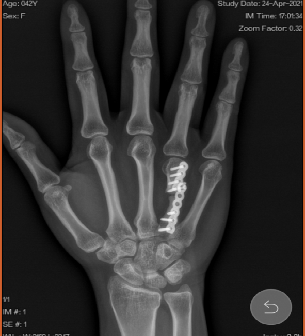

病例2:女性患者,42岁,1年半之前因摔伤到宁波某医院诊疗,行“第4掌骨骨折切复钢板螺钉内固定术”。术后一年半复查发现内固定钢板断裂并骨折未愈合,因此患者转来我院就诊。 入院前影像学检查提示:右手第4掌骨骨折线清晰,边缘硬化,内固定钢板折断。

手术方案:内固定拆除,取髂骨,第4掌骨植骨钢板螺釘内固定术。术中给予骨不连两端截去硬化灶;截取髂骨塑型嵌入。

经管医师汇报了手术过程中,特别是植骨过程中的重要细节,如如何取髂骨应对去除骨折端硬化灶后出现的1cm宽缺隙。对于该患者,还需要继续加强术后沟通交流,很可能会采取PRP治疗以促进骨折愈合。

刘立春副院长建议,术后加支具,有利于骨折部位的愈合。